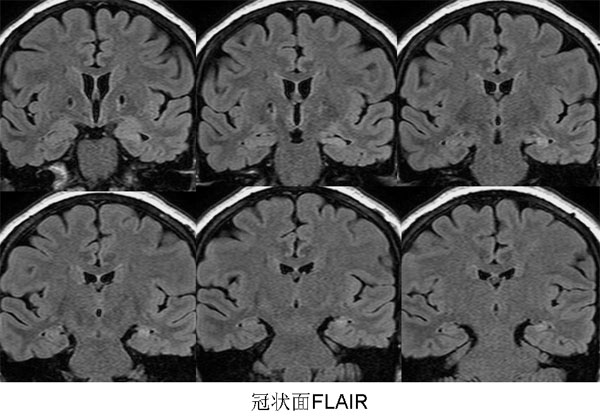

以下是引用三博在2009-9-10 12:42:00的发言:[br]病理:左侧海马硬化。[br]苍白球软化灶。[br]左侧海马信号增高,体积变小,右侧海马信号未见明显异常,